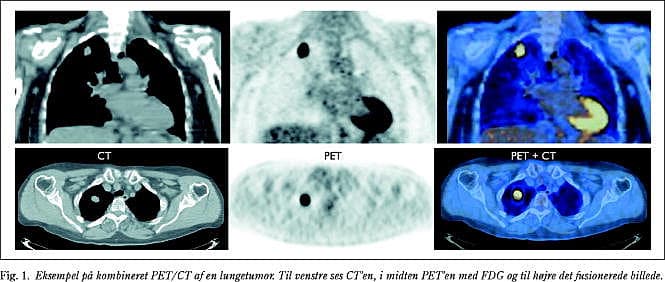

Ved hvilke problemstillinger vil vi få gavn af morfologisk information i form af en CT? For PET/CT vil hovedindikationen utvivlsomt være onkologiske problemstillinger, hvor en nøjagtigere lokalisering af tumoren og metastaserne vil have betydning for den videre terapi. Med såkaldt koincidens- eller »hybrid«-PET med konventionelt gammakamera vil CT være tilsvarende værdifuld (Fig. 1).